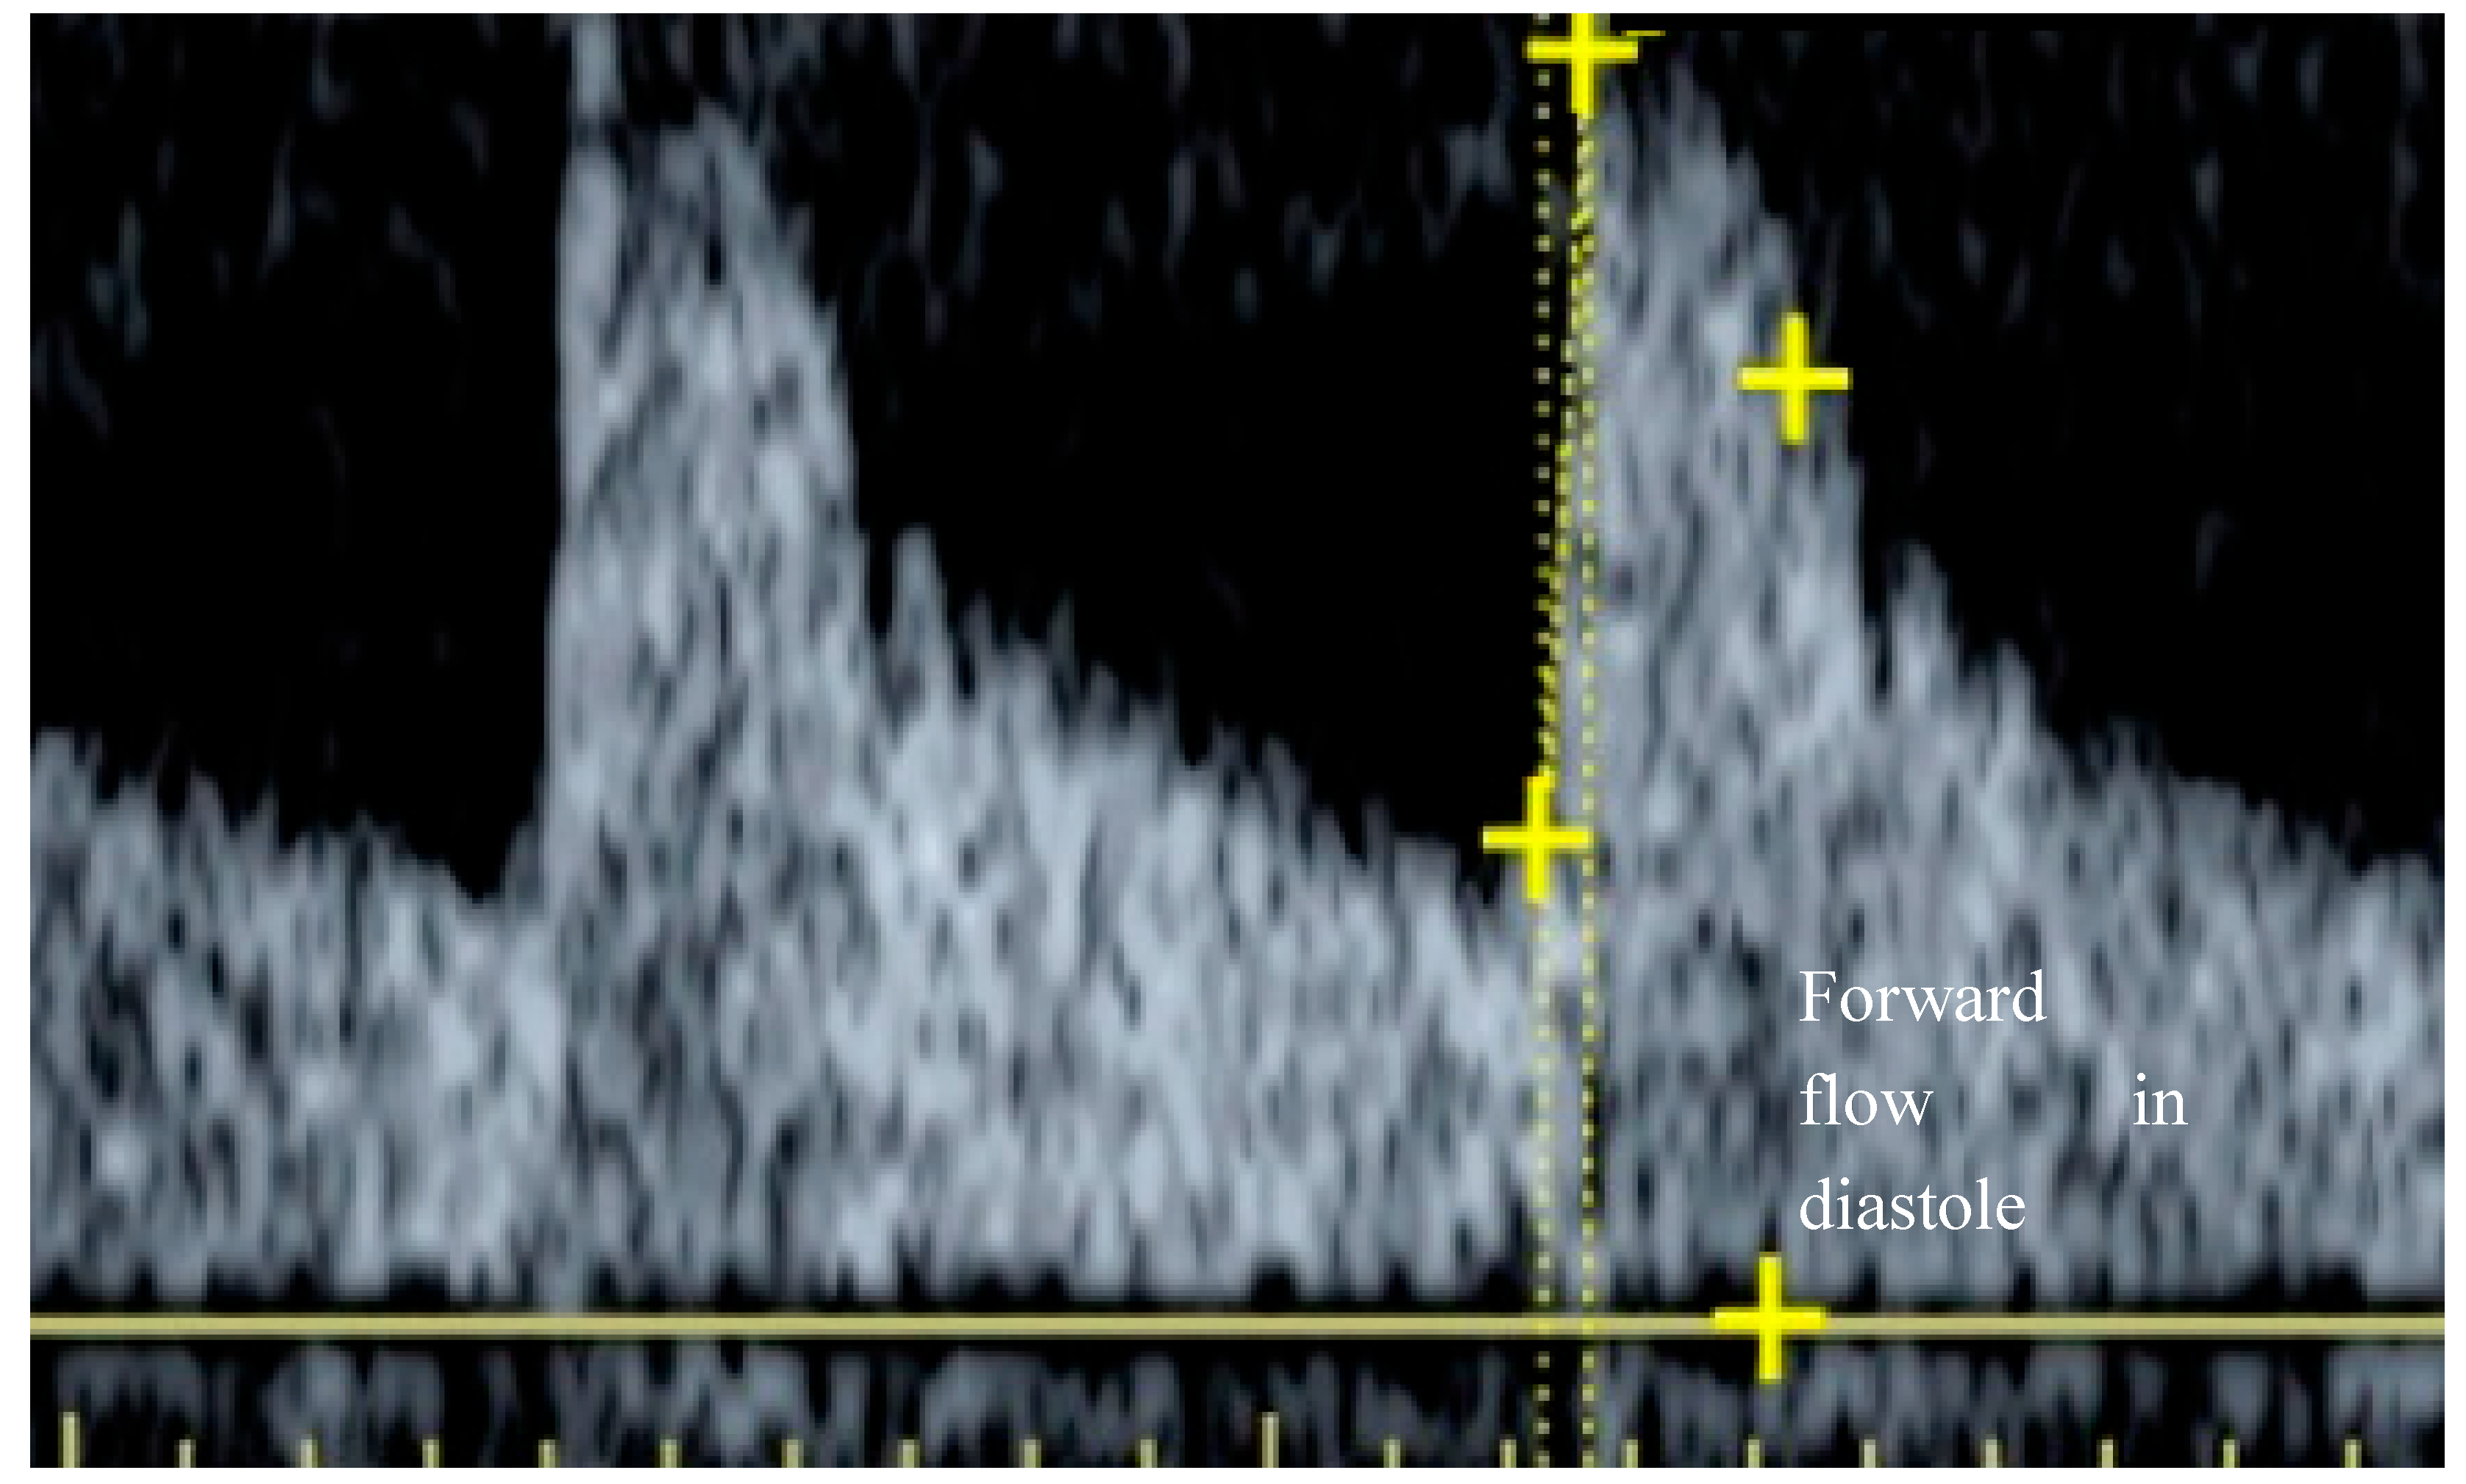

- Ratio of diastolic to systolic blood pressure

- Combined effect of interstitial and venous pressure

- Ratio of lumen area in systole and diastole at the sample site

- Interstitial pressure (increased recoil during diastole if iP raised)